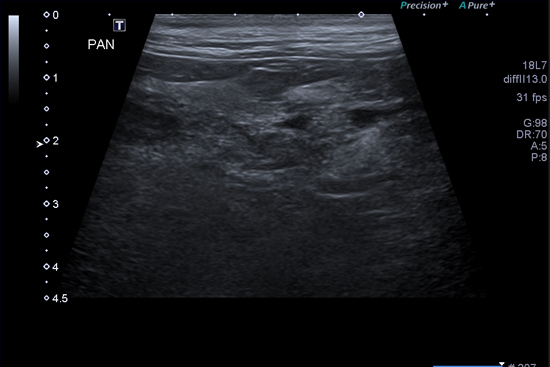

췌장염

췌장은 소화효소를 분비하는 기능과 다양한 호르몬을 분비하는 기능을 가지고 있습니다. 이러한 췌장에 염증이 생기는 경우 소화효소의 누출로 주변 조직으로의 심한 염증을 유발하게 되며, 심한 경우 췌장의 괴사 및 전신 염증을 일으켜 사망에 이를 수 있습니다. 극심한 통증 및 구토 등 소화기증상을 나타냅니다. 췌장염의 원인은 특발성 외 다양한 기저질환에 의해서도 발생할 수 있으며 정확한 진단과 합병증 관리가 중요합니다.